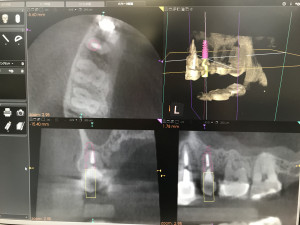

このインプラント治療をする前に特殊なレントゲン撮影(歯科用CT)で徹底的に骨の形を分析して、正しいインプラント埋入位置を計画します。

治療計画したインプラント埋入位置をデータ化してそれを3Ⅾプリンターに送るのです。このデータと、実際の口の中のデータ(現在は歯型模型)をPC上で融合させるのです。そうするとサージカルステントといってインプラント手術用の重要な道具を作ることが出来ます。いわばこれは「物差し」です。